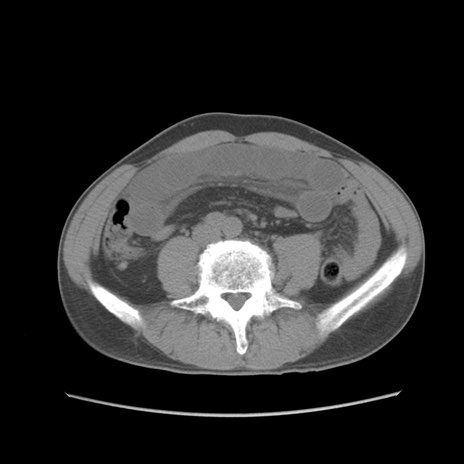

症例56 CT(横断像)

脂肪ウインドウ